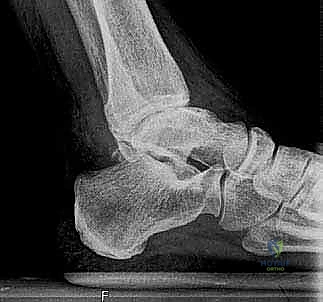

لفهم أهمية جراحة استبدال الكاحل، يجب أولاً فهم تشريح هذا المفصل المعقد. يتكون مفصل الكاحل من التقاء ثلاث عظام رئيسية:

1. عظمة الظنبوب (Tibia): وهي عظمة الساق الكبرى التي تشمل الجزء الداخلي والعلوي من الكاحل.

2. عظمة الشظية (Fibula): وهي عظمة الساق الصغرى التي تشكل الجزء الخارجي من الكاحل.

3. عظمة الكاحل (Talus): وهي العظمة السفلية التي ترتكز عليها عظام الساق وتعمل كمفصلة للحركة.

تُغطى نهايات هذه العظام بطبقة ناعمة ومرنة تسمى الغضروف المفصلي، والذي يعمل كوسادة لامتصاص الصدمات وتقليل الاحتكاك أثناء الحركة. عندما يتآكل هذا الغضروف، تبدأ العظام بالاحتكاك ببعضها البعض، مما يسبب ألماً مبرحاً وتورماً وتيبساً.

2. الفصال العظمي (Osteoarthritis)

يُعرف أيضاً بخشونة المفاصل أو التآكل التدريجي. يحدث نتيجة التقدم في العمر والاستهلاك المستمر للمفصل بمرور الزمن. على عكس مفصل الركبة أو الورك، يعتبر الفصال العظمي الأولي في الكاحل أقل شيوعاً، وعادة ما يكون مرتبطاً بعوامل أخرى.

- تشوه شكل الكاحل: انحراف في شكل القدم أو الكاحل نتيجة انهيار العظام أو تآكل الغضروف غير المتكافئ.

1. التقييم والتحضير قبل الجراحة

يتم إجراء فحوصات شاملة تشمل الأشعة السينية (X-rays)، والأشعة المقطعية (CT scan) لإنشاء نموذج ثلاثي الأبعاد لكاحل المريض. يساعد هذا د. هطيف في اختيار الحجم الدقيق للمفصل الصناعي وتحديد زوايا القطع بدقة متناهية.